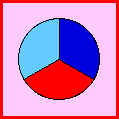

Sistema radiográfico ICDAS

(Radiografía Bite-Wing) |

|

Sano |

|

R0 |

No hay

radiolucidez |

|

|

Estadios

iniciales * |

|

RA1 |

Radiolucidez en

1/2 externa del esmalte |

|

|

RA2 |

Radiolucidez

en la 1/2 interna del esmalte ± UAD

(Unión amelo-dentinaria) |

|

|

Se lo considera aún un estadio

inicial porque no hay dentina

infectada ) |

|

RA3 |

Radiolucidez

limitada al 1/3 externo de la

dentina |

|

|

Estadio

moderado

(En este estadió

comiemza la infección de la dentina por bacterias orales) |

|

RB4 |

Radiolucidez que

alcanza hasta el 1/3 medio de la

dentina |

|

|

Estadios

severos

(Infección franca de la dentina) |

|

RC5 |

Radiolucidez que

alcanza hasta el 1/3 interno de la

dentina, clínicamente cavitada

|

|

|

RC6 |

Radiolucidez en

la pulpa, clínicamente cavitada

|

|

*

Nota- La

mayoría de lesiones confinadas al esmalte no

se ven en las radiografías.

|

Tabla 4: Clasificación

radiográfica ICDAS